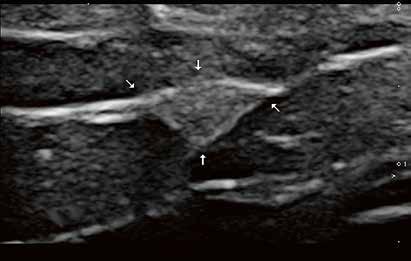

Ziel der Forschungen an der Universität Bordeaux war die hochaufgelöste und detailreiche Darstellung spezieller Hirnareale, wie des Hippocampus oder des Claustrum. Diese Regionen hatte Prof. Tourdias schon am 7T-System bei seinem Aufenthalt an der Stanford-Universität studiert. Nun war es mit der AiCE-Technologie möglich, vergleichbar aufgelöste Bilder auch bei 3T in akzeptabler Untersuchungszeit zu erzeugen (siehe Abb. 5 a und b).

Natürlich lassen sich die Vorteile einer höheren Auflösung nicht nur in der klinischen Forschung nutzen, sondern sind auch dazu geeignet, bei-

Abb. 5 a + b: Hochaufgelöstes Bild des Hippocampus; 0,15 mm x 0,15 mm; 2 mm Schichtdicke; rechts mit AiCE-Rekonstruktion. Mit freundlicher Genehmigung des Unversitätsklinikums Bordeaux. Abb. 6 a + b: Hochaufgelöstes Bild des Knies; 0,15 mm x 0,15 mm (interpoliert); 1 mm Schichtdicke; rechts mit AiCE-Rekonstruktion.

42 // VISIONS 31

spielsweise einen Knorpelschaden im Knie im Detail zu zeigen.

Durch die alternative Nutzung des SNR-Gewinns durch AiCE werden MR-Untersuchungen ohne Auflösungsverlust beschleunigt. Der große klinischen Vorteil bei diesem Einsatz von AiCE ist, dass es bei Patienten zu weniger Artefakten durch Bewegung kommt. Die Quote von Wiederholungsaufnahmen wird deutlich reduziert bei gleichzeitiger Steigerung des Bildqualität. Vereinfacht gesagt steigt die Untersuchungskapazität des MRTs. Zur Beschleunigung der Untersuchungsdauer eignet sich besonders das neue Compressed-SPEEDER-Verfahren, das völlig unabhängig von Spulentyp und Untersuchungsrichtung zum Einsatz kommt.

A T1-Gewichtung; Auflösung 0,35 mm x 0,35 mm; 59 Sek.

B T2-Gewichtung; Auflösung 0,3 mm x 0,3mm; 57 Sek.